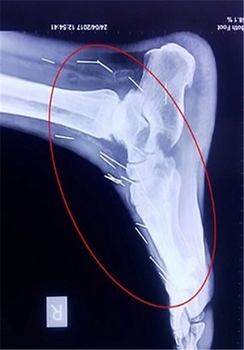

این مرد هندوستانی که «بادریلال مینا» نام دارد و در ایالت راجستان زندگی میکند، 75 سوزن در گردن، دستها و پاهایش وجود داشت.